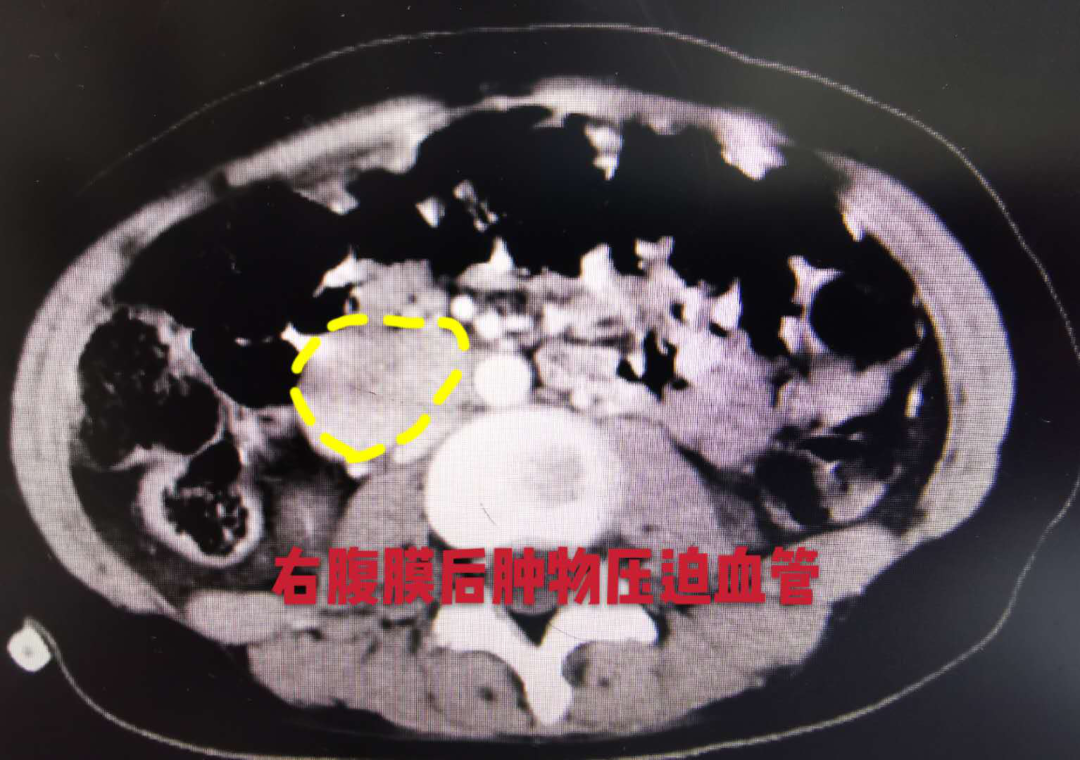

最初小李以为是自己猛然加强运动身体不适应,没想到短短数天内,情况竟然迅速进展为全下肢无力,走路疼痛不稳,感觉和运动功能部分丧失。家人马上将小李送到当地医院进行检查,检查结果着实把全家人吓了一跳,小李的第8胸椎和第8后肋存在不规则肿块!为进一步确诊治疗,家人带小李来到中山大学肿瘤防治中心就诊,进一步检查发现小李全身上下竟然有两处“炸弹”!小李的胸8椎体及左侧第8后肋骨肿物达68mm×67mm×37mm,由于肿物压迫脊髓,导致小李下肢神经功能丧失;同时合并右侧腹膜后肾下级血管旁肿物约39mm×28mm,压迫后方的下腔静脉和内侧的腹主动脉。

小李的手术由曾维安教授带领欧超鹏医师全程做好麻醉管理,在泌尿外科周芳坚教授团队指导下,由董培副主任医师主刀。虽然小李的肿物血供非常丰富,并与腔静脉粘连紧密,术中血压一过性升高达180/120mmHg,但在多学科手术团队的默契配合下,小李右腹膜后的“炸弹”终于拆除成功!肿物切除后,小李的血压、心率即刻降至正常。